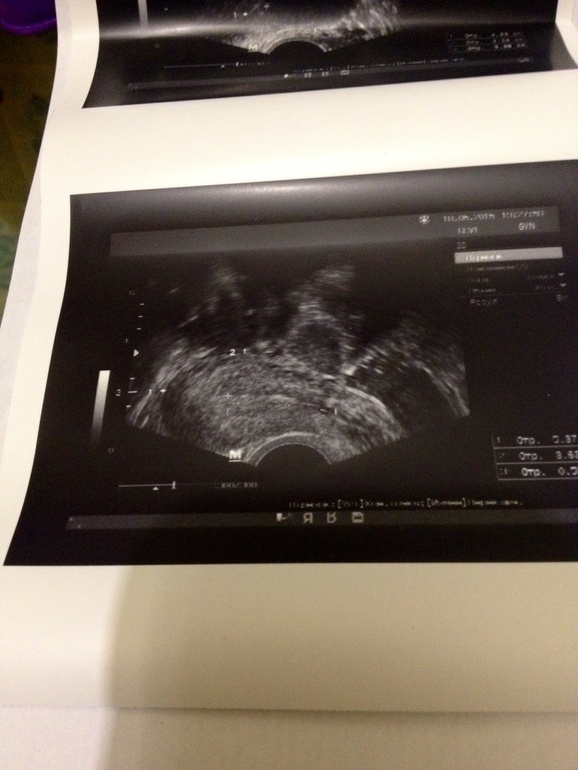

Привет) побывала на узи. Врач так себе попался... Ничегошеньки не сказал, говорит все с врачом решать будешь. Вот такое получила узи. Киста левого яичника. 34мм. Я вот смотрела его дома и в матке увидела точку в левом углу? Что это? Плод,который не заметил врач? Ошибка датчика? И может это все таки б и киста ЖТ?) я ж все надеюсь!)))) спасибо всем за понимание и ответы))))))

У тебя киста фолликулярная. У меня тоже было. У тебя ведь тесты при О полосатятся? Но видимо у тебя не лопается фолликул и перерастает в кисту. От этого бывают частые задержки в циклах. Тебе наверное скорее нужна стимуляция. То, что матка больше скорее тоже результат кисты. При эндометрии толщиной в 4 мм беременность исключена.

У меня аж 2 месяца киста держалась. Около 4 см была диаметром. Знаю такое дерьмо :( да с месячными выходит. У меня была функциональная киста, у тебя по видимому из за гормонов. Да и к тому же у тебя сколько уже циклов не получается. :( мне кажется сто и эндометрий тоже немного тонкий для фазы цикла. Скорее проблема не только в том что овуляция не получается но и в том что эндометрий не благополучный доя имплантации. Очень тонкий.... Возможно у тебя киста еще в прошлом цикле образовалась и не узла с месячнысии от того и эндометрий не нарос в этом цикле. В любом случае тебе необходим хороший репродуктолог. И конечно, всегда держу за тебя кулачки и наблюдаю за твоими новостями ;)